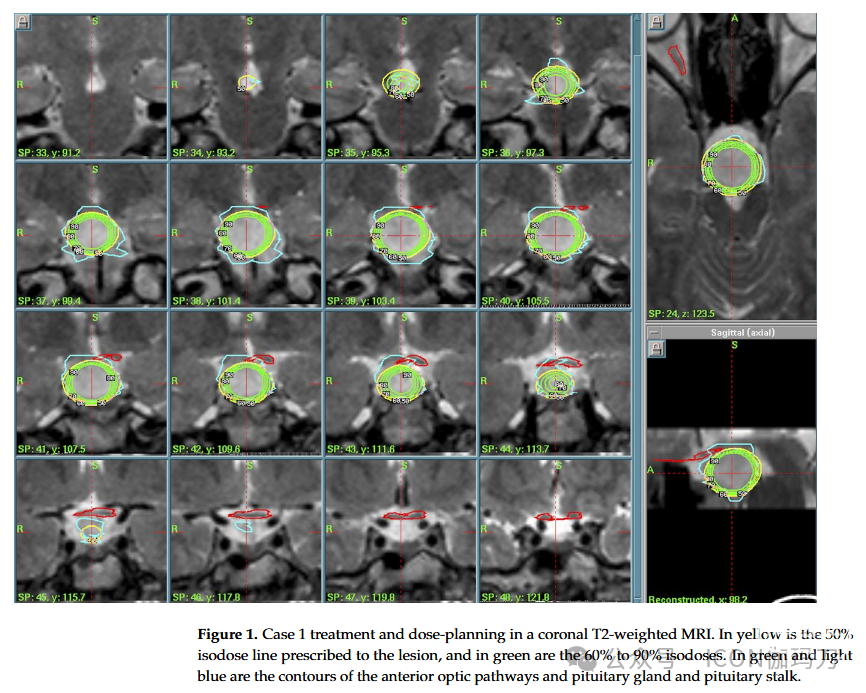

病例1:一名24岁的男性表现出长期的痴笑和不良癫痫发作史。他在上世纪90年代被诊断出患有缓慢增长的HH。由于药物治疗(5种药物)无法控制癫痫发作,在患者拒绝手术后提出了GKRS。病变相对较大:磁共振图像(MRI)显示下丘脑结节呈错构瘤状,向右到达右侧第三脑室,形成并决定右半侧视交叉的血流。在尾部,它推进到斜坡后区,并与基底动脉相连。2004年,为了避免过度照射视交叉和视觉通路,提出了一种放射外科治疗方案(外周等剂量线(PI)为50%,处方剂量(PD)为11 Gy,最大剂量(MD)为22 Gy,积分剂量为148.7毫焦耳(mJ), 12 Gy体积7.71 cc)。由于患者拒绝开颅手术,且出现耐药性癫痫发作,建议采用GKRS治疗。病变很大,位于关键结构(视交叉,基底动脉)附近,使放射外科成为更安全的选择。该病例在多学科背景下进行了讨论。(图1)。

图1。病例1在冠状位T2加权MRI上的治疗和剂量计划。黄色为病变处方的50%等剂量线,绿色为60%至90%等剂量线。绿色和浅蓝色是前部视神经通路和垂体和垂体柄的轮廓。

术后过程顺利,患者出院后无新的神经功能障碍。患者接受了临床和影像学随访,最后一次MRI(2020年8月)未见病变再生,无病理强化。患者目前使用2种抗癫痫药物(左乙拉西坦和卡马西平)治疗,对残余单纯性部分癫痫发作控制良好。下一次随访磁共振将于今年进行。